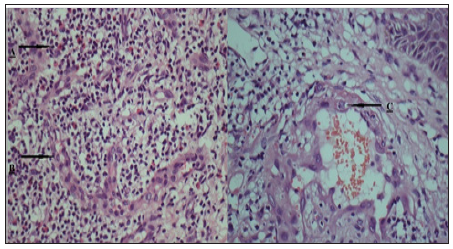

Parotidgland and subcutaneous tissue was normal. No Arterio– Venous malformation was seen on colour and pulsed Doppler. Histopathology revealed proliferation of small and medium sized vessels showing lobular architecture with perivascular inflammatory infiltrate of lymphocytes and eosinophils. Their lining showed plump endothelial cells with abundant eosinophilic cytoplasm and intracytoplasmic vacuoles (Figures 4 & 5).

Figure 5: A.Perivascular inflammatory infiltrate of lymphocytes and eosinophils. B. Plump endothelial cells with abundant eosinophilic cytoplasm. C. Endothelial cell showing intracytoplasmic vacuoles. (H & E 40X).